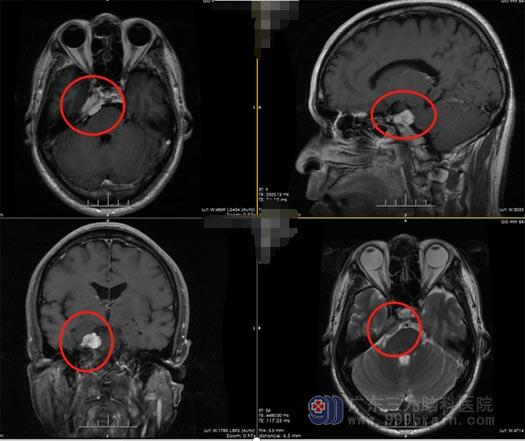

57岁的周大叔是湖南人,10个月前因为出现右侧面部麻木,在当地诊所检查, 医生考虑颈椎病,予以口服药物治疗。周大叔一直严格遵照医嘱按时服药,然而日子一天过去,周大叔并没有感觉到症状有好转。持续近10个月后,周大叔的面部麻木症状反而愈发严重,家人劝周大叔去大一点的医院检查,这回真的发现了问题:头颅MR提示为“桥脑右侧前缘异常信号,考虑三叉神经瘤可能”。

周大叔开始焦急了,治疗了近一年,最后却发现误诊了,颈椎病变成了脑肿瘤!这次他谨慎一些了,经多方打听后,周大叔最终选择来到广东三九脑科医院,找到了鲁明副院长,鲁明初步考虑是“右侧岩斜区脑膜瘤”可能。入住神经外五科后,进一步头颅MR检查,提示为右侧岩斜区-鞍旁占位性病变,考虑脑膜瘤可能,待排神经鞘瘤。